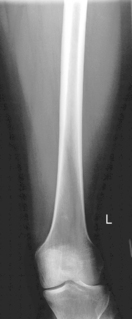

Note: For adults, a second smaller IR of either the hip or the knee should be taken on trauma patients to demonstrate both knee and hip joints to rule out possible fractures.

• Rotate entire lower limb internally ≈5° for AP of midfemur and distal femur, and 15° internally for true AP to include hip.

• Lower border of IR ≈5 cm (2″) below knee to include knee joint adequately (see AP Unilateral Hip for proximal femur, p. 156).

Note: For adults, take a second smaller IR of lateral hip or lateral knee if both joints are areas of interest.